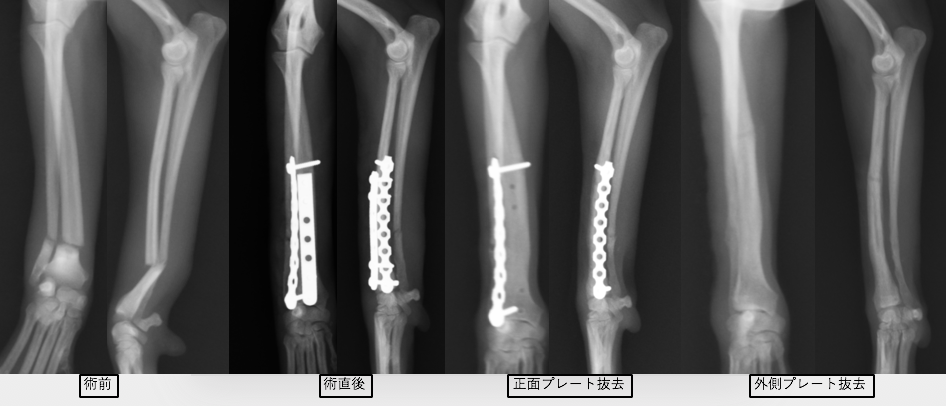

トイプードル9歳の橈尺骨骨折です。1.5mmスクリューを使用しています。

上の3症例ともにやや中央寄りの先端部の橈尺骨の横骨折(遠位骨幹部橈尺骨横骨折)です。直線のプレートを使用しています。